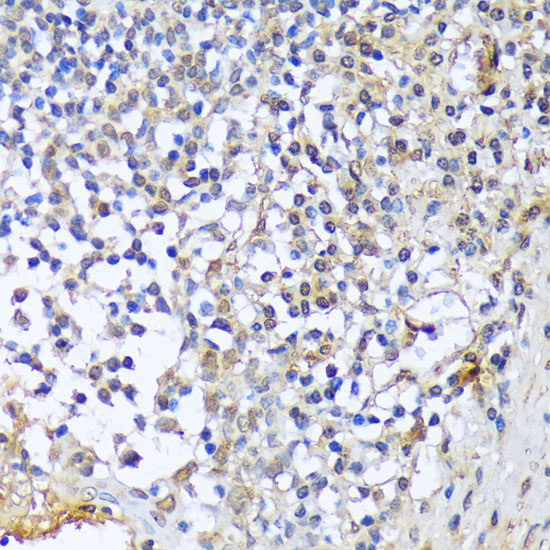

Immunohistochemistry of paraffin-embedded rat ovary using A1CF antibody at dilution of 1:100 (40x lens).

Immunohistochemistry of paraffin-embedded human tonsil using A1CF antibody at dilution of 1:100 (40x lens).

Immunohistochemistry of paraffin-embedded mouse brain using A1CF antibody at dilution of 1:100 (40x lens).